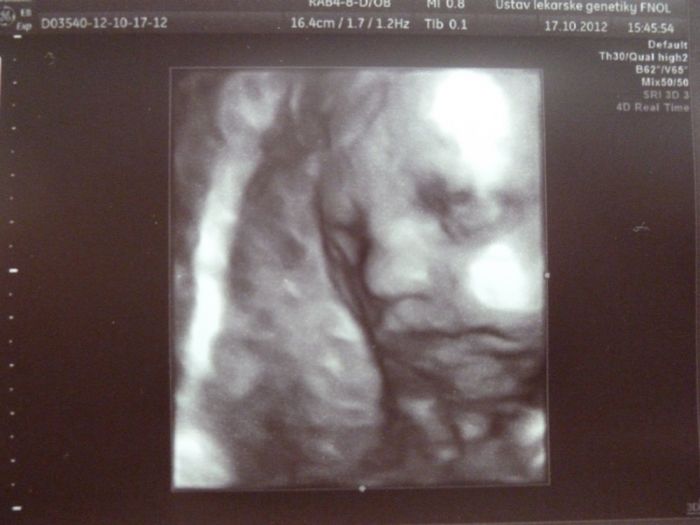

Tak máme za sebou ten 3D ultrazvuk, bála jsem se že nebudeme nic vidět, ale malá byla vidět krásně, je to nejkrásnější miminko na světě už teď

- jako samozdřejmě pro každou mamku to její

. Paní doktorka nám ji teda potřetí potvrdila, tak snad se z ní už ten kluk nevyklube

, máme 13.minut video a 4 fotky, jsem fakt spokojená, je tak sladkááá

. No fotečky vám sem dám dvě, na jedné se pěkně mračí, asi ji to už nebavilo

.